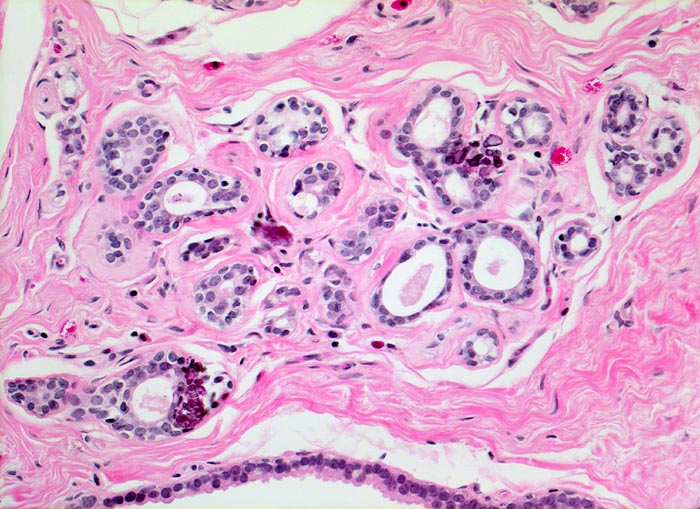

Rundlicher blauvioletter Mikrokalk in den Azini benigner Drüsenläppchen.

Kolumnarzellveränderung: erweiterte Drüsen ausgekleidet von hochprismatischem Epithel mit apikalen Nasen (snouts) gefüllt mit Sekret und teilweise assoziiert mit Mikrokalk.

Alle Drüsen zeigen eine erhaltene äussere abgeflachte Myoepithelschicht mit hellem Zytoplasma.